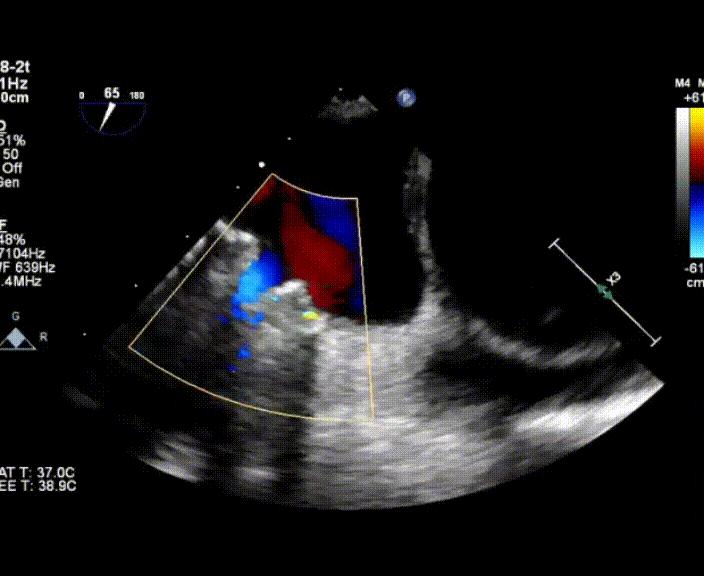

術(shù)中首先在局麻下穿刺股動脈、股靜脈,完成心導(dǎo)管檢查評估后轉(zhuǎn)為全麻,在食道超聲引導(dǎo)下穿刺房間隔,穿刺成功后將加硬導(dǎo)絲送入左上肺靜脈建立軌道,根據(jù)患者病情行球囊預(yù)擴張后植入6mm孔徑房間隔造孔支架,經(jīng)透視及食道超聲評估支架左右盤展開良好,夾持于房間隔兩側(cè),固定穩(wěn)定、位置良好,食道彩超顯示房水平右向左為主分流,分流孔直徑符合預(yù)期大小,心導(dǎo)管檢查評估達到預(yù)期效果,釋放造孔支架。術(shù)后12h患者下床活動,恢復(fù)順利,擬于近日完善術(shù)后評估后出院。